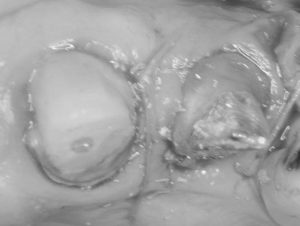

ピエゾサージェリーという超音波機器を今年導入してから、歯周外科がそれまでよりもスピーディーに行えるようになりました。前歯の審美障害と歯周治療希望で来院された患者さんです。犬歯の下がった歯肉は完全でなくてもある程度カバーできればいいというご希望だったので歯肉移植はしませんでした。その労力が省けた分、歯周組織再生療法を同時に行うことができました。術式も今年の3月に学んだばかりの方法で行いました。術後まだ10日なので歯肉の形は落ち着いていませんが、数か月待ってブリッジの型取りに行ければと思います。いつも準備やアシストをしてくれるスタッフには本当に感謝です。とても一人ではできないと常々思います。

根面被覆と再生療法を同時に